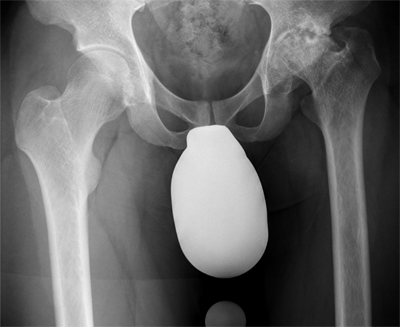

Ein Beispiel: 34 –jähriger Patient mit Morbus Perthes

( Absterben des Hüftkopfes im Kindesalter )

Hier ist der obere Anteil des Knochens bereits durch schmerzbedingte Entlastung osteoporotisch. Die höhere Sicherheit des Einwachsen des Schaftes bringt die Prothese in Standardmaß